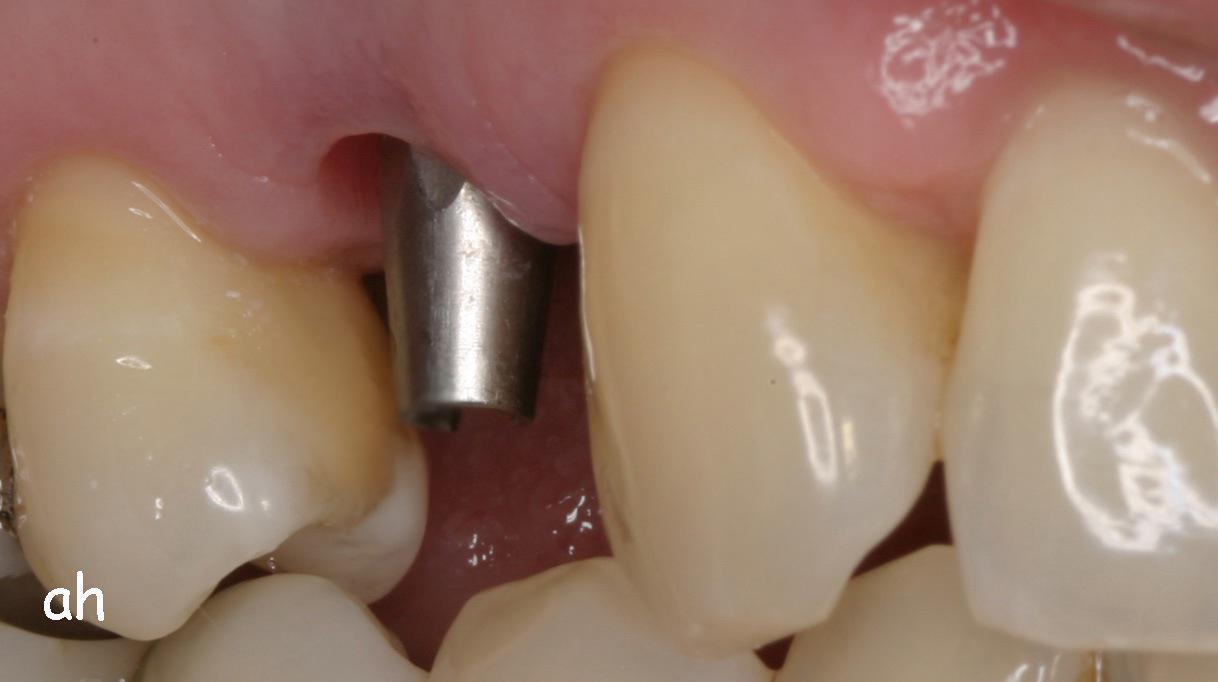

Exemple 3: Un implant à la place d'une incisive latérale supérieure droite. Sur cette image on voit le moignon en titane qui est vissé sur l'implant.

Exemple 3: Puis sur ce moignon, la couronne en céramique est scellée.

Exemple3: La couronne en place.